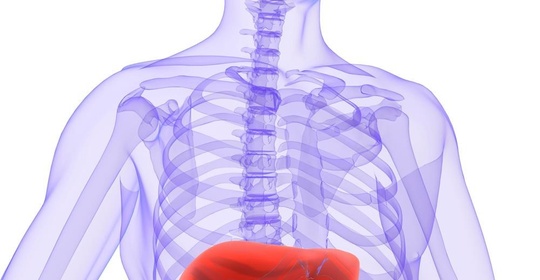

新生兒肝脾腫大:常見原因、評估與醫學指導